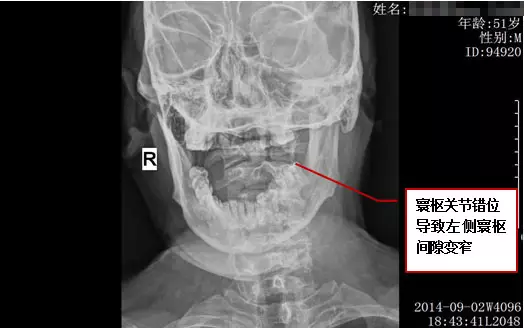

段先生,男,51岁,云南人,于2014年9月2日慕名而来,由我院赖志刚院长接诊。

反复颈部疼痛10年,于久伏案、寒冷时颈痛加重,伴头晕、右上肢痛麻2年,加重2月。

客观检查结果: 复位前 拍片时间: 2014年9月2日 18:43